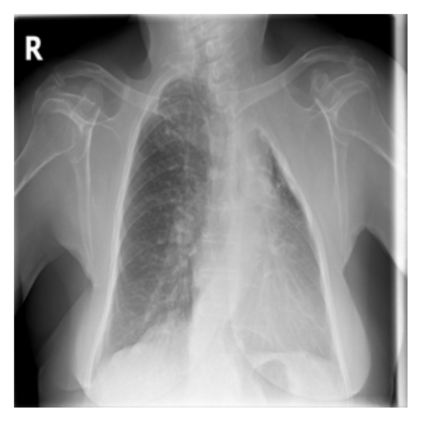

The evaluation of infectious disease processes on radiologic images is an important and challenging task in medical image analysis. Pulmonary infections can often be best imaged and evaluated through computed tomography (CT) scans, which are often not available in low-resource environments and difficult to obtain for critically ill patients. On the other hand, X-ray, a different type of imaging procedure, is inexpensive, often available at the bedside and more widely available, but offers a simpler, two dimensional image. We show that by relying on a model that learns to generate CT images from X-rays synthetically, we can improve the automatic disease classification accuracy and provide clinicians with a different look at the pulmonary disease process. Specifically, we investigate Tuberculosis (TB), a deadly bacterial infectious disease that predominantly affects the lungs, but also other organ systems. We show that relying on synthetically generated CT improves TB identification by 7.50% and distinguishes TB properties up to 12.16% better than the X-ray baseline.